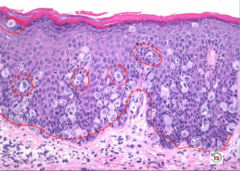

Vulvar Carcinoma

Malignant, arising from SQUAMOUS epithelium...very RARE Presentation: leukoplakia (must be distinguished from lichen) HPV type - HPV 16/18 - arises from vulvular intraepithelial neoplasia (VIN) = dysplasia (high N:C, hyper chromatic, pleomorphic, mitotic) - often reproductive age Non-HPV type - arising from lichen sclerosis - elderly women